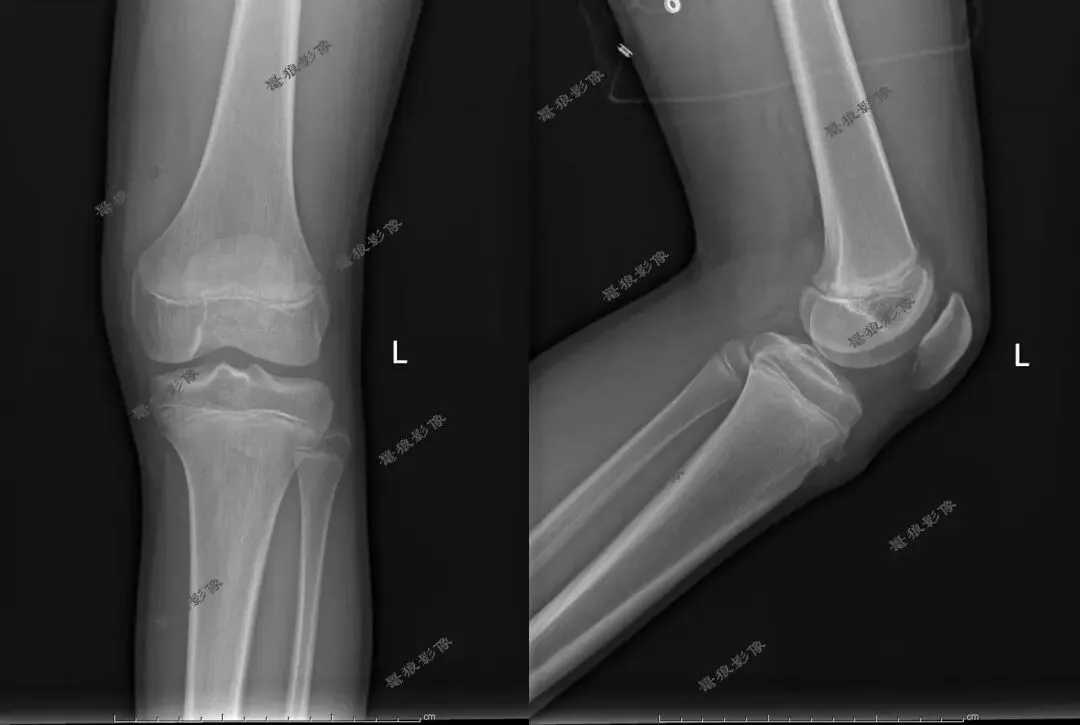

M,13y。左膝疼痛月余,近日加重就诊。

X线平片(双侧):

考虑左胫骨结节骨软骨炎,请结合临床,建议进一步检查。

X线:早期可见髌韧带附着点软组织肿胀、髌韧带增厚;中期胫骨结节骨骺密度增高、不规则、边缘模糊,可出现骨碎片;修复期可见骨骺融合或遗留游离骨片。